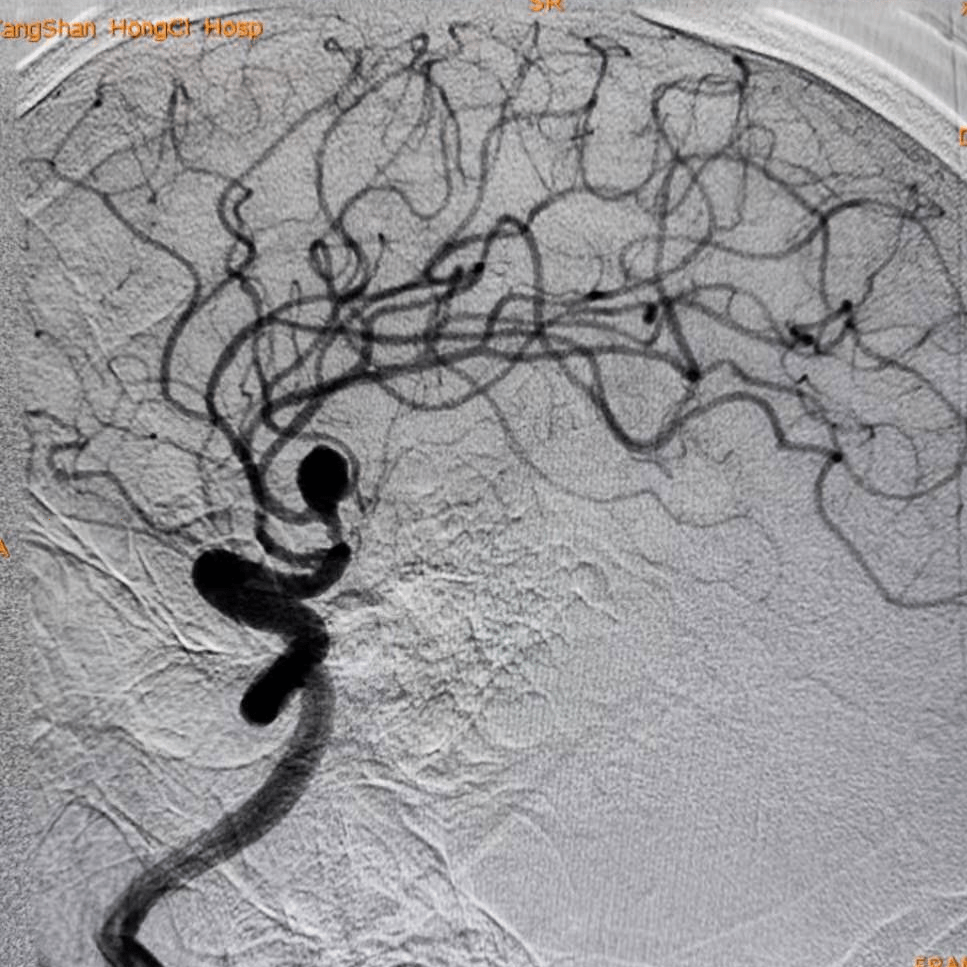

【器械百科】史赛克neuroform atlas颅内支架系统

万曙教授团队:atlas支架辅助下血管内治疗夹闭术后复发的奇大脑前动脉